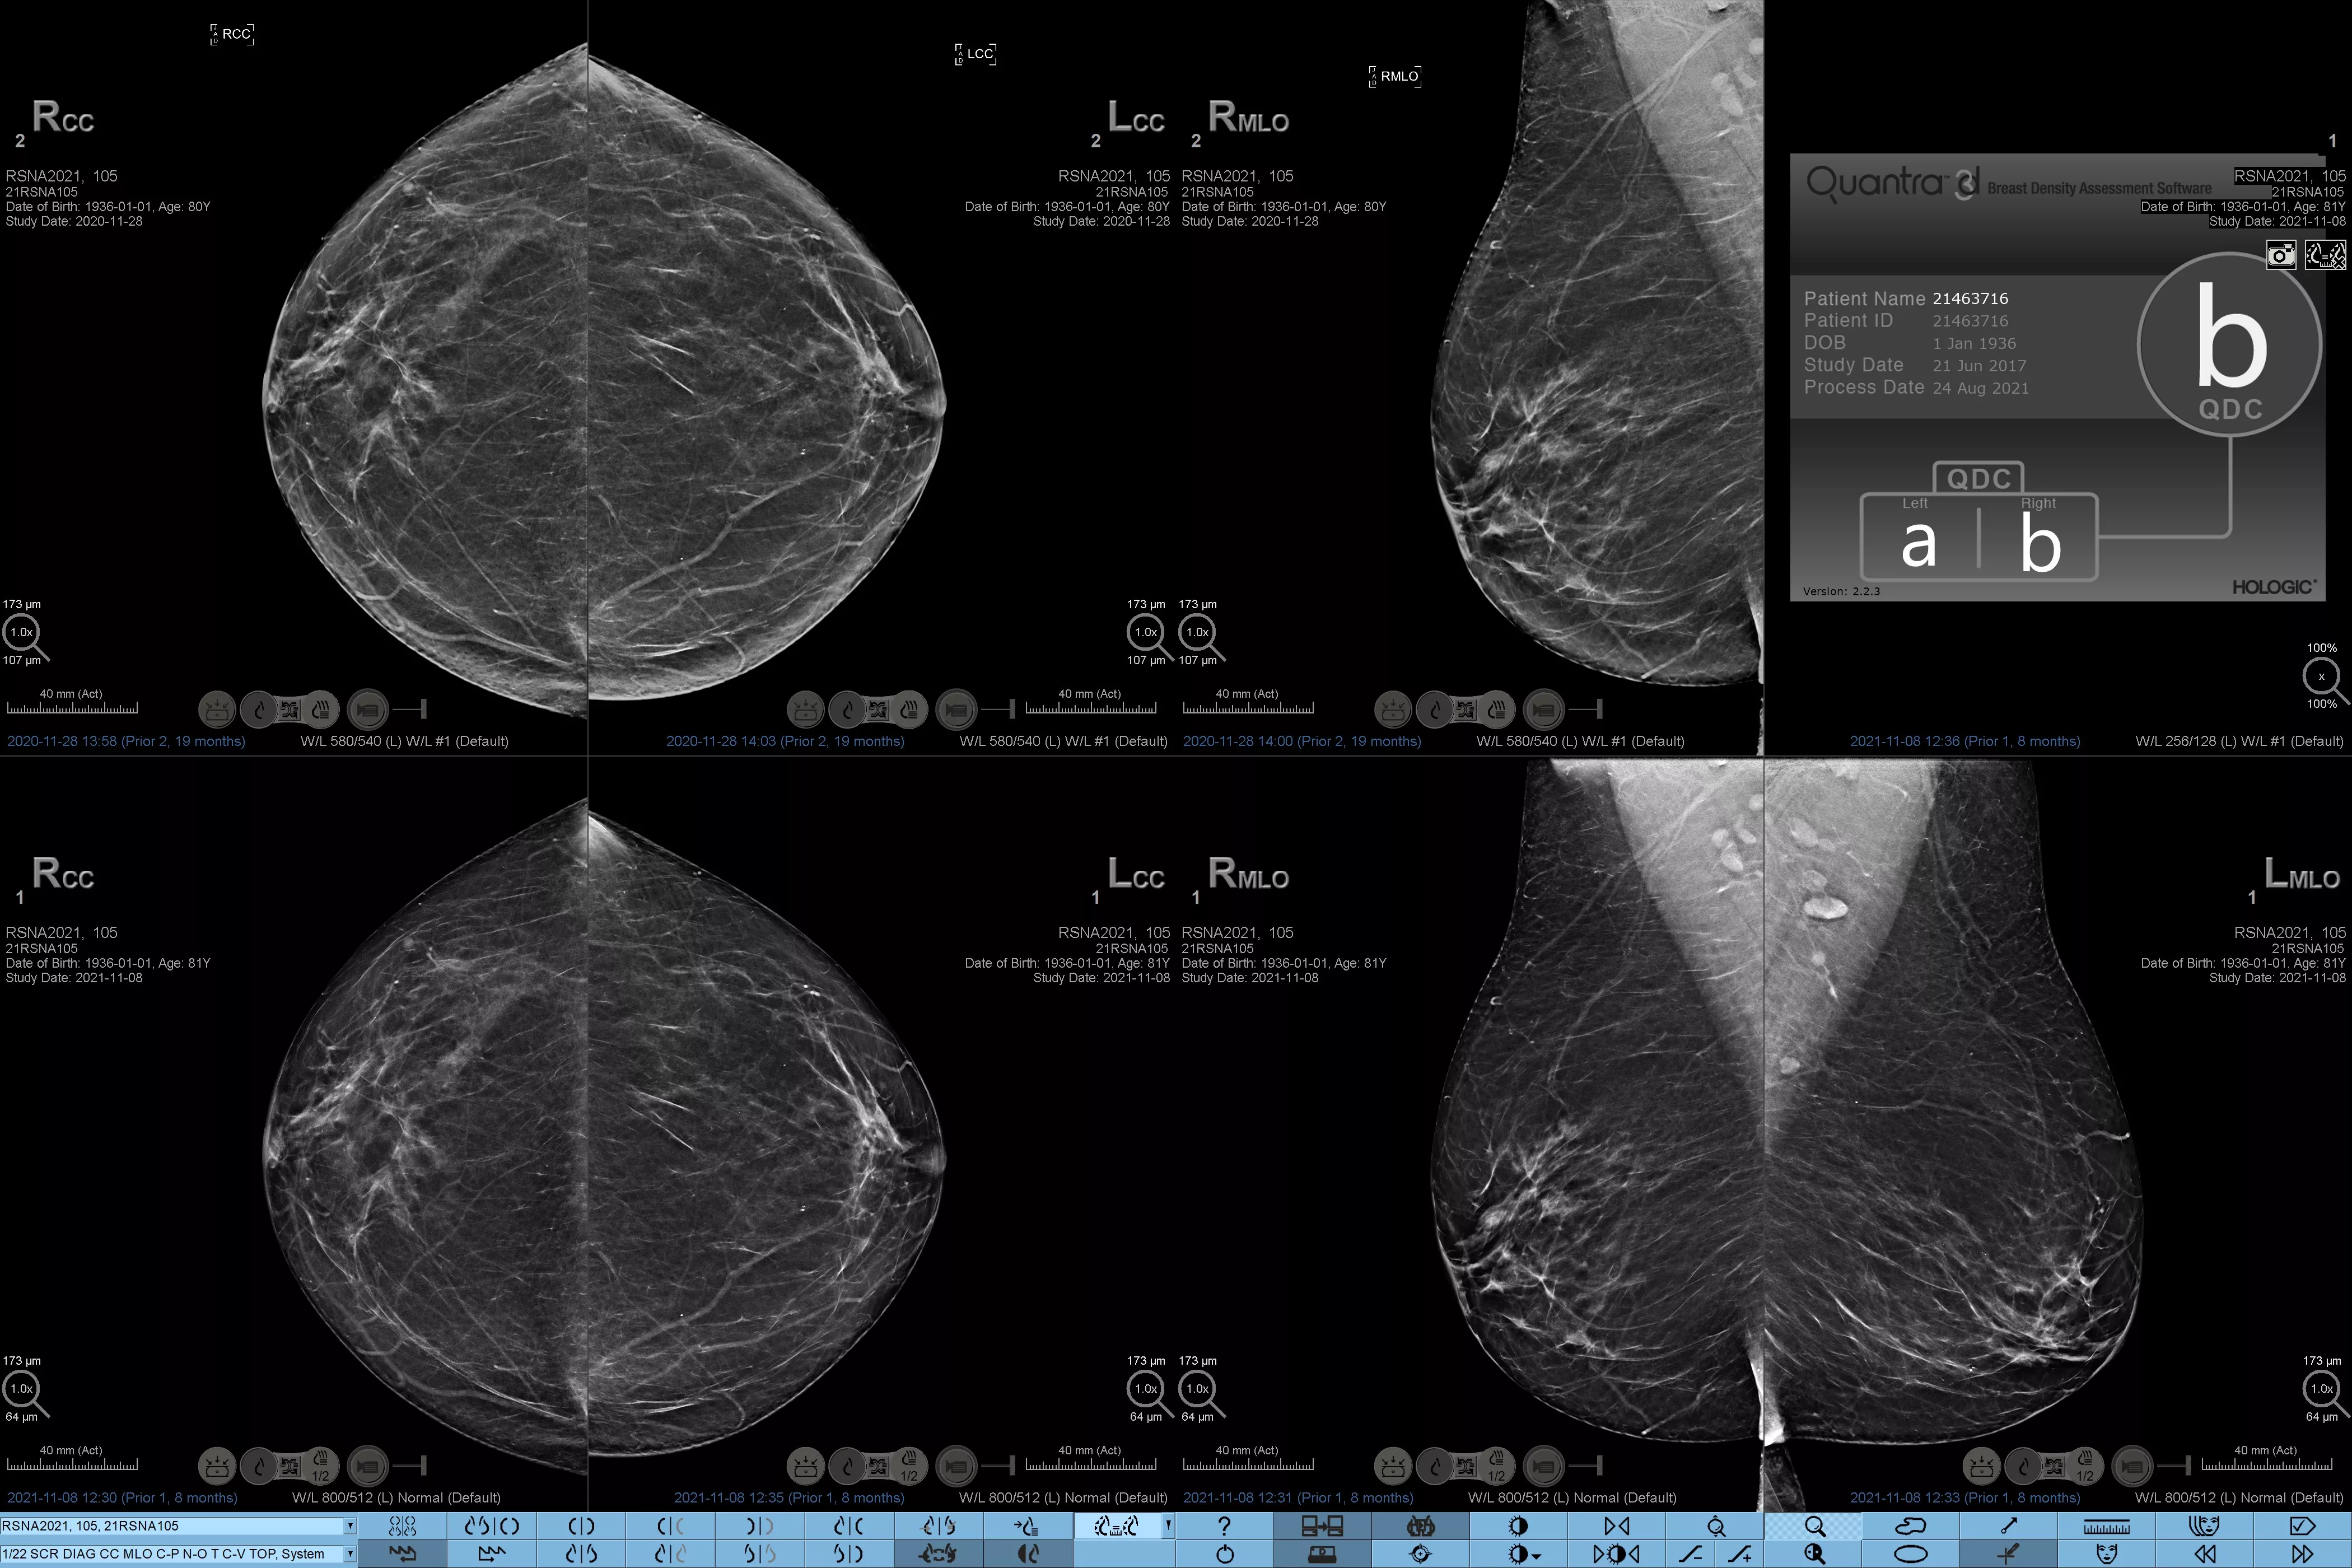

Higher breast density is known to increase a woman’s risk for breast cancer.1 The need for accurate, unbiased analysis is therefore critical. Powered by machine learning, Quantra technology software analyses both 2D™ and tomosynthesis images for distribution and texture of parenchymal tissue. It categorises breasts in four breast composition categories consistent with guidance from the American College of Radiology (ACR) BI-RADS Atlas 5th Edition.2

Objective machine learning algorithm that assigns breast density category based on analysis of breast tissue texture and patterns.

Quantra software’s unbiased algorithm analyse both 2D and tomosynthesis images to support your analysis by:

• Overcoming subjectivity in visual assessment, providing more consistent, and more reliable scoring.*

*Scores are based on ACR BI-RADS categories, in line with the revised guidance by the American College of Radiation (ACR) BI-RADS Atlas 5th Edition. This accounts for pattern and texture, compared with volume, when determining density.